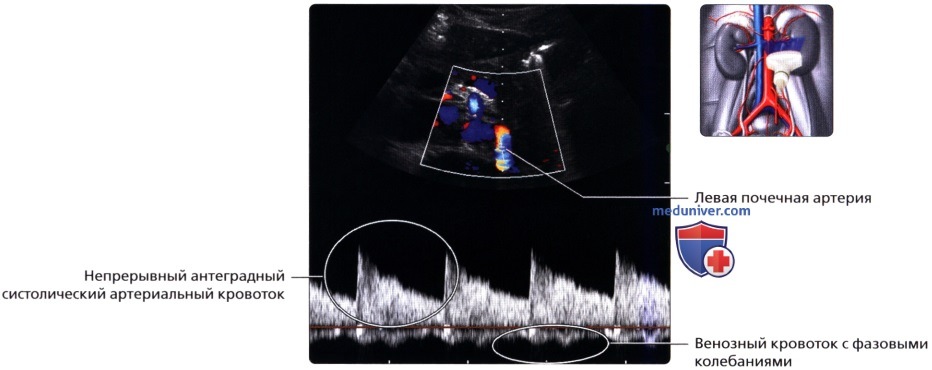

Неотъемлемой частью обследования почек стало ультразвуковое допплерографическое исследование, дающее возможность наблюдать за кровотоком в почечных сосудах. Делая УЗИ сосудов почек, можно установить на ранней стадии стеноз артерий, сбои в кровоснабжении, сосудистые сбои.

УЗДГ (УЗИ сосудов почек) выполняется в положении больного лежа на боку или сидя. Каких-то особенностей у этой процедуры нет. Врач также перемещает датчик по поверхности кожи пациента, внимательно изучая постоянно меняющиеся на мониторе изображения.

Ультразвуковое исследование при заболеваниях сосудов почечного кровообращения

К этим заболеваниям относятся поражения почечной вены и артерий. Это могут быть сужения (стенозы), закупорка тромбом (тромбозы), а также нарушение целостности сосудов при травмах.

| Патология | Цель назначения УЗИ | Ультразвуковые признаки |

| Тромбоз почечной вены | Цель при ультразвуковом исследовании сосудов одна и сводится в первую очередь к тому, что необходимо определить тип и калибр пораженного сосуда. На втором этапе необходимо обнаружить зоны с кровоизлияниями и инфарктом почки и оценить степень поражения. | На первой стадии болезни на УЗИ видна увеличенная почка со сниженной эхогенностью по периферии (в корковом веществе). Через 1 – 2 недели периферия становится эхогенной. Иногда из-за очаговых кровоизлияний появляются небольшие гипоэхогенные участки. При помощи допплерографии выявляется снижение или отсутствие кровотока в почечной вене. Если развивается «обходной» венозный кровоток, то эхогенность возвращается к норме, однако почка может уменьшиться в размерах. |

| Тромбоз почечной артерии | Когда поражена одна ветвь почечной артерии, на УЗИ виден эхогенный неоднородный участок, который переходит в гипоэхогенный в течение нескольких дней. Если тромб находится в основном стволе почечной артерии, то вначале почка увеличена в размерах. При длительном отсутствии кровоснабжения почка атрофируется и уменьшается в размерах, становясь гипоэхогенной. Окончательный диагноз ставится на основе результатов допплеровского исследования. При допплерографии отмечается снижение или отсутствие кровотока в артерии с тромбом. | |

| Стеноз почечной артерии | Зоны инфаркта почки на УЗИ визуализируются как гипоэхогенные треугольные участки в паренхиме. Когда зоны инфаркта замещаются соединительной тканью (рубцом), на УЗИ они становятся гиперэхогенными. |